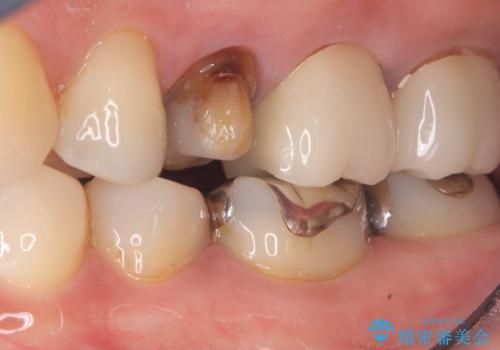

唇側マージン不適なこと説明し、審美性・適合性に優れたセラミッククラウン(スタンダード)でのやり替えとなりました。

治療途中、一度仮歯に置き換えを行っています。